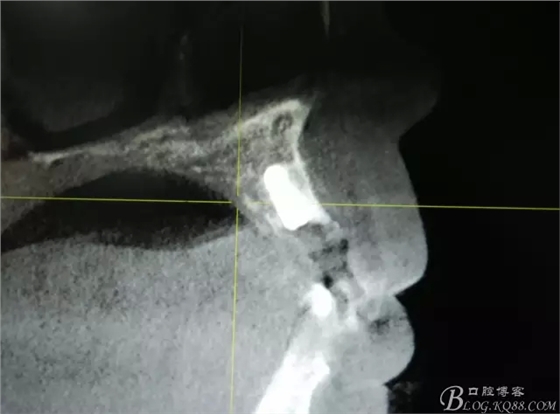

患者、楊xx、男、49歲。主訴:左側(cè)前牙拔除半年,活動義齒修復(fù)四個月,要求種植修復(fù)。??茩z查:21缺失,牙槽粘膜厚度正常。CBCT檢查:高度16mm,寬度7mm.術(shù)前簽知情同意書。

圖2.CBCT的三維成像及縱剖面、水平面影像